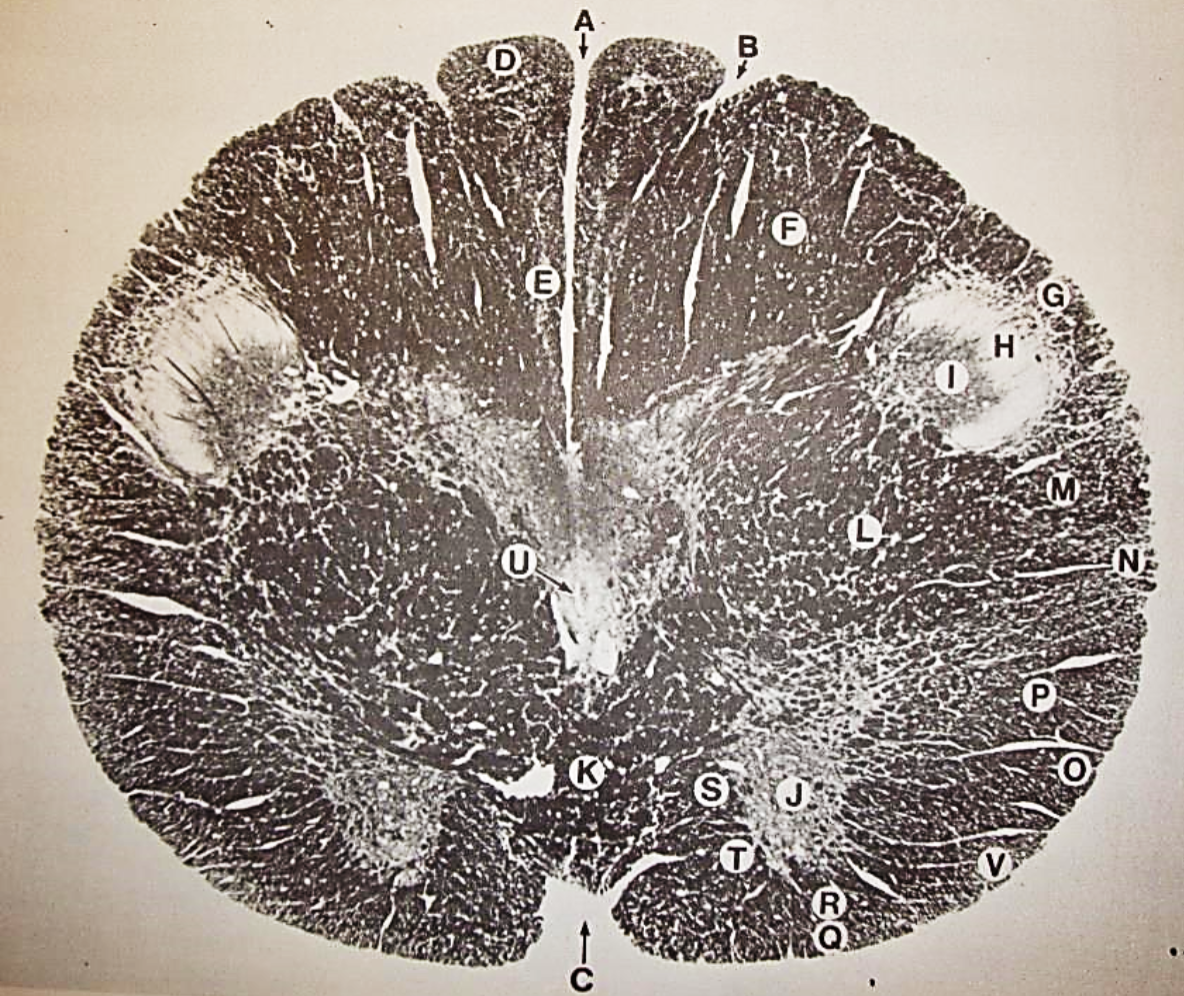

A

fasciculus gracilis

B

gracile nucleus

C

fasciculus cuneatus

D

cuneate nucleus

F

internal arcuate fibers

G

decussation of internal arcuate fibers

H

medial lemniscus

I

hypoglossal nucleus

J

dorsal motor nucleus vagus

K

solitary fasciculus

L

solitary nucleus

M

dorsal longitudinal fasciculus

N

spinal trigeminal tract

O

spinal trigeminal nucleus

P

posterior spinocerebellar tract

Q

anterior spinocerebellar tract

R

spinal lemniscus

S

lateral vestibulospinal tract

T

rubrospinal tract

U

lateral reticular nucleus

V

medial accessary olivary nucleus

W

pyramidal (corticospinal) tract

X

arcuate nucelus

Y

medial longitudinal fasciculus

Z

tectospinal tract

a

fascicles of hypoglossal nerve